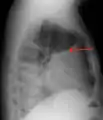

الأشعات

عادةً (في الوضع الطبيعي) لا يمكن رؤية الفراغ الموجود بين طبقتي الغشاء البِلُّوري: الغشاء البِلّوري الجداري (أي المُبَطّن للقفص الصدري) والغشاء البِلّوري الحشوي (أي الذي يغطي الرئة). والارتشاح البِلّوري يتسرب ليملأ الفراغ الموجود بين هاتين الطبقتين. وبما أن الارتشاح البِلّوري له كثافة مماثلة لسوائل الجسم (أو الماء)، فإنه من الممكن رؤيته من خلال صور الأشعات. وبما أن للارتشاح كثافة أعلى من كثافة بقية الرئة (حيث أن الرئة تحتوي على الهواء) فإنه ينجذب إلى الجزء السفلي من التجويف البِلّوري. يتصرف الارتشاح البِلّوري وفقا لديناميات السوائل الأساسية، متسقاً مع شكل الرئة وتجويف الصدر. وإذا كان التجويف البِلّوري يحتوي على كل من الهواء والسائل (hydropneumothorax)، فإن السائل سيكون له مستوى أفقي "fluid level" بدلاً من أن يتسق مع مساحة الرئة.[2] لأشعات الصدر المُلتَقَطة في الوضع الجانبي lateral decubitus position (أي مع وضع المريض على جانبه أثناء التقاط الأشعة) حساسية أكبر، ويمكنها الكشف عن وجود الارتشاح في حال وجود حتى اقل من 50 مل من السوائل. يلزم وجود 300 مل على الأقل من السوائل حتى يتسنى لأشعات الصدر في الوضع القائم (upright position) الكشف عن بعض علامات الارتشاح البِلّوري (على سبيل المثال، التحام الزاوية بين الضلوع والحجاب الحاجز costophrenic angle).